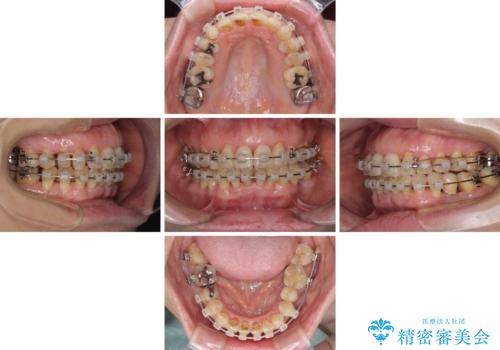

口元の出っ張りとデコボコを改善したい

- 矯正装置

- クリアブラケット

- 治療期間

- 2年

- 近医にてインプラント治療を行った後に矯正治療を希望され、来院された患者様です。

口元の突出感とデコボコが気になっているとのことでしたが、インプラントが既に3本埋入されていたため、抜歯矯正による口元を引っ込めることができない状況でした。

近医での歯周病治療の影響でブラックトライアングルが発現していたため、IPR(歯と歯の間を削る)で隙間を改善しつつ、インプラントを固定源に歯列全体を後方へ移動させることとしました。